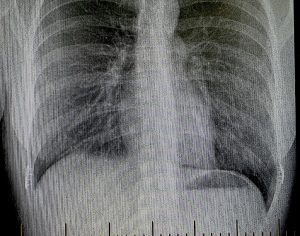

The relationship of rib 9 to the lung can be summarized as follows:

At rest (quiet breathing):

- Lung reaches rib 6 at the midclavicular line

- Rib 8 at the midaxillary line

- Rib 10 posteriorly

With deep inspiration:

- The lung may descend 1–2 rib levels, potentially reaching rib 9 laterally

Equally important is the position of the pleura, the outer lining of the lung. The parietal pleura extends lower than the lung itself:

- Rib 8 at the midclavicular line

- Rib 10 at the midaxillary line

- Rib 12 posteriorly

Thus, at rib 9—particularly along the midaxillary line—one is often below the lung but still within the pleural cavity.

Key anatomic takeaways:

- Rib 9 is generally below the lung at rest

- Rib 9 lies within the pleural reflection

- Deep inspiration can bring lung tissue down to rib 9